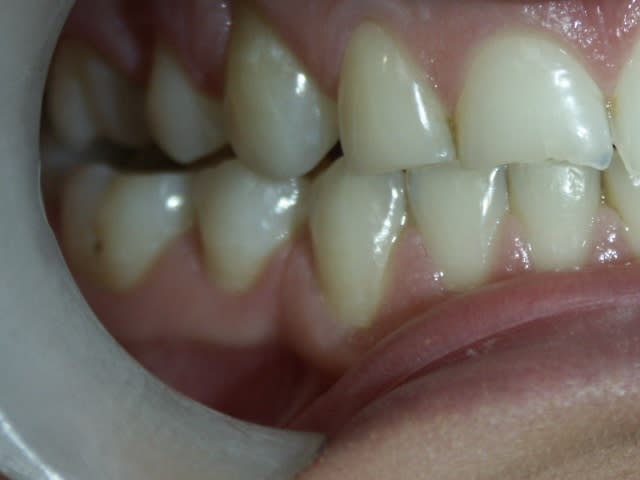

Ci-joint les photos d'un patiente qui s'est présentée pour refaire les angles cassés sur 11 et 12.

Les dents sont vitales, pas d'antécédents de choc ou de tics et manies pouvant expliquer le phénomène.

Les molaires sont en partie en inocclusion, en particulier les 15-16/45/46, et légèrement côté G. Pas de douleur à l'ATM.

Elle a bénéficié d'un traitement ODF pendant l'adolescence pour tenter de corriger une tendance à la classe III squelettique. Il y a un terrain familial à la Cl III (encore plus marquée chez le frêre). Les dénudations radiculaires au maxillaire en sont certainement une séquelle (ainsi qu'un brossage intempestif) du traitement.

Sur les photos, on remarque ce qui ressemble à une asymétrie de la branche horizontale de la mandibule, qui se traduit par l'articulé inversé côté droit.

Moi j'aurais envie de retablir une protection canine. Les latéralités ont l'air de se faire sur les incisives, normal que ça casse. Elle a dû faire une petite chute de ski quand même,ou prendre un coup de boule sur la mandibule qui a provoqué une fissure et puis le morceau est parti plus tard.